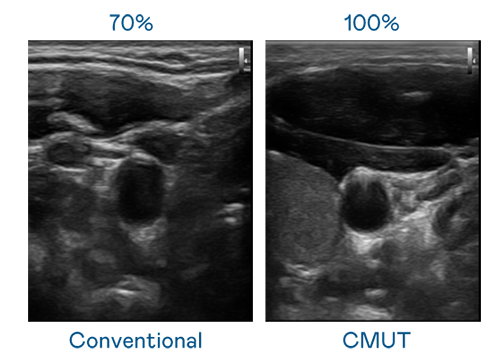

CMUT 技术是一种用电容式微机电元件来产生超音波讯号的技术。与传统 PZT 压电式技术相比,CMUT 频宽增加 30%,更宽频的超音波讯号让影像解析度大幅提升,是实现高影像品质医疗超音波扫描、促进精准医疗发展的关键技术。

超音波影像的解析度高低,首先取决于探头能发出的讯号频宽。小勐拉99厅 CMUT 可提供高清晰的超音波讯号,提供高频宽、高灵敏度、影像纹理细节更高的超音波影像,协助医护人员缩短影像判读时间及利用精准的医疗影像进行诊断。